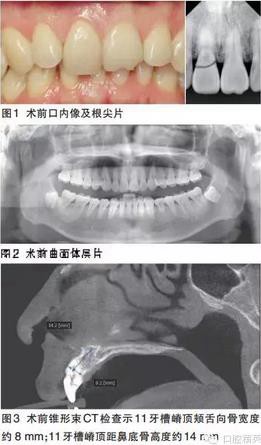

牙體:11冠折,斷面位于齦下,松動Ⅲ度,牙齦有觸痛,21切1/3部分缺損,無明顯松動。牙列:完整恒牙列。咬合:前牙區(qū)內(nèi)傾型深覆Ⅱ度。牙周:未見明顯牙石,牙齦無明顯紅腫,個別牙面可見少量黃褐色色素沉積。黏膜:唇緣線對稱,唇紅色澤自然,無皸裂,口角區(qū)黏膜無糜爛。頜面部:面部左右對稱,無腫脹、疼痛,面部比例協(xié)調(diào),下頜運(yùn)動正常。開口度:正常。

根尖片示11牙頸部可見折裂影像。

曲面體層片示38、48低位埋伏阻生。

錐形束CT示11牙根唇側(cè)骨壁較薄約0.5~1mm;11牙槽嵴頂頰舌向骨寬度約8mm;11牙槽嵴頂距鼻底骨高度約14mm;11牙槽嵴長軸與牙冠長軸方向夾角約34°。